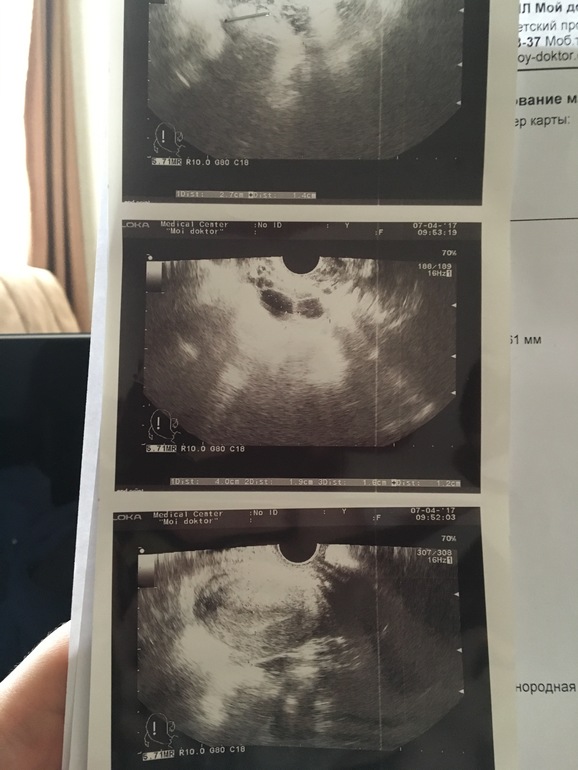

нет в узи от 07 числа написано На момент исследования признаки секреторной фазы мц. мультифолликулярных яичников. Узи от 04 апреля, на момент исследования признаки 2 фазы цикла. На узи от 28 марта, на момент исследования эхографические признаки нормального статуса в малом тазу, соответствуют 2 фазу цикла, косвенные признаки произошедшей овуляции.

Узи от сегодня лежит в машине. Но там как и 7 числа фолликул. Короче чему верить незнаю

это от 28 марта

от 4 апреля

от 7 апреля